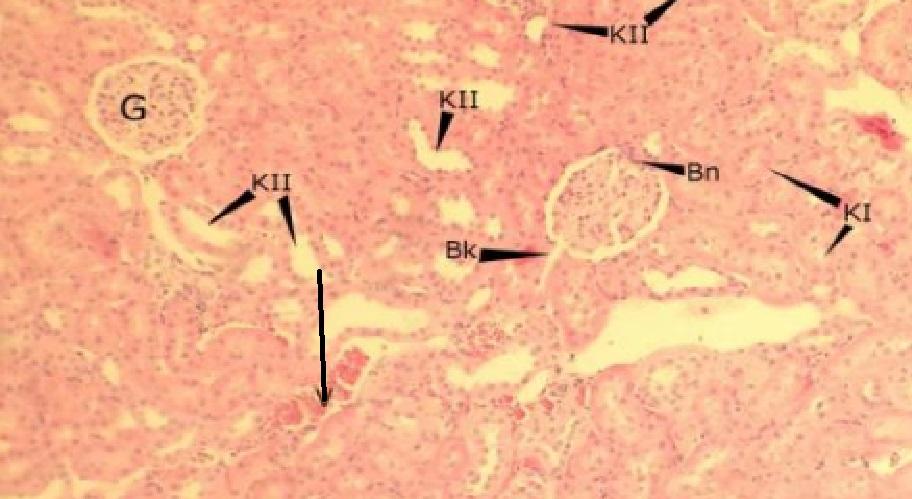

biegun naczyniowy (nerka)

Pytanie 576

biegun kanalikowy kłębuszka (nerka)

Pytanie 577

tętniczka doprowadzająca (nerka)

Pytanie 578

tętnica międzyzrazikowa (nerka)

Pytanie 579

żyła (nerka)

Pytanie 580

żyła międzyzrazikowa (nerka)